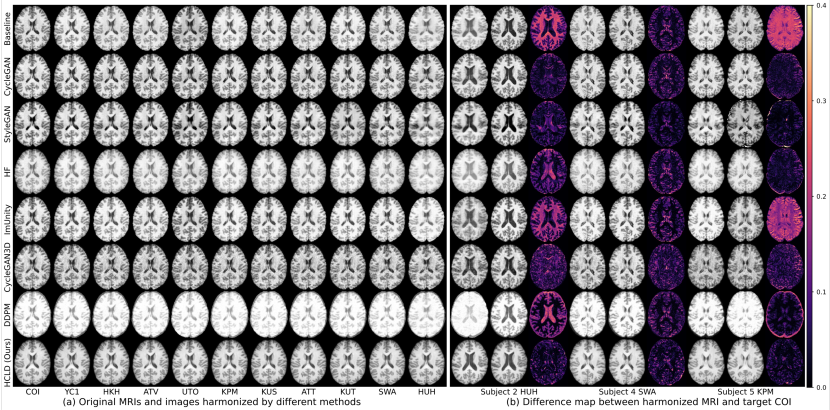

Figure 4: Axial view (a) sample visualization results for SRPBS Subject 8 across 11 sites, and (b) difference map between each harmonized MRI and its ground truth for three SRPBS subjects (i.e., Subject 2 from HUH, Subject 4 from SWA, and Subject 5 from KPM).

The qualitative analysis of sample MRIs from one subject across all 11 sites, as depicted in Fig. 4 (a), along with the difference map between harmonized source sites and target site COI from 3 samples in Fig. 4 (b), further validate the histogram comparison results in Figs. 2-3. The baseline MRI scans, before harmonization, exhibit significant variations in intensity and contrast across the different sites. Although most harmonization methods manage to standardize the style of the MRIs, our proposed HCLD method demonstrates superior performance by aligning the style more closely to that of the target site, COI. Our approach also produces MRIs with significantly higher image quality than the 3D methods, such as CycleGAN3D and DDPM. Additionally, when compared to 2.5D and 2D methods (i.e., ImUnity, CycleGAN, and StyleGAN), the HCLD generates results with fewer artifacts. Among the 10 source sites, HUH presents a particularly challenging case due to its distinct deviation from the target site COI. Our HCLD effectively harmonizes HUH to COI, whereas most other methods fail on this site, as demonstrated by the orange line in Fig. 2 and the corresponding HUH columns in Fig. 4. More visualizations can be found in Figs. S1-S18 of Supplemental Materials. Also, Figs. S1-S9 in Supplementary Materials illustrate that our HCLD achieves superior harmonization outcomes in the coronal view, while some 2D methods (e.g., StyleGAN and HF) exhibit noticeable artifacts or spatial discontinuity under this view. This is because these methods only perform slice-by-slice harmonization in the axial view, highlighting the advantage of harmonization on the 3D volume level.